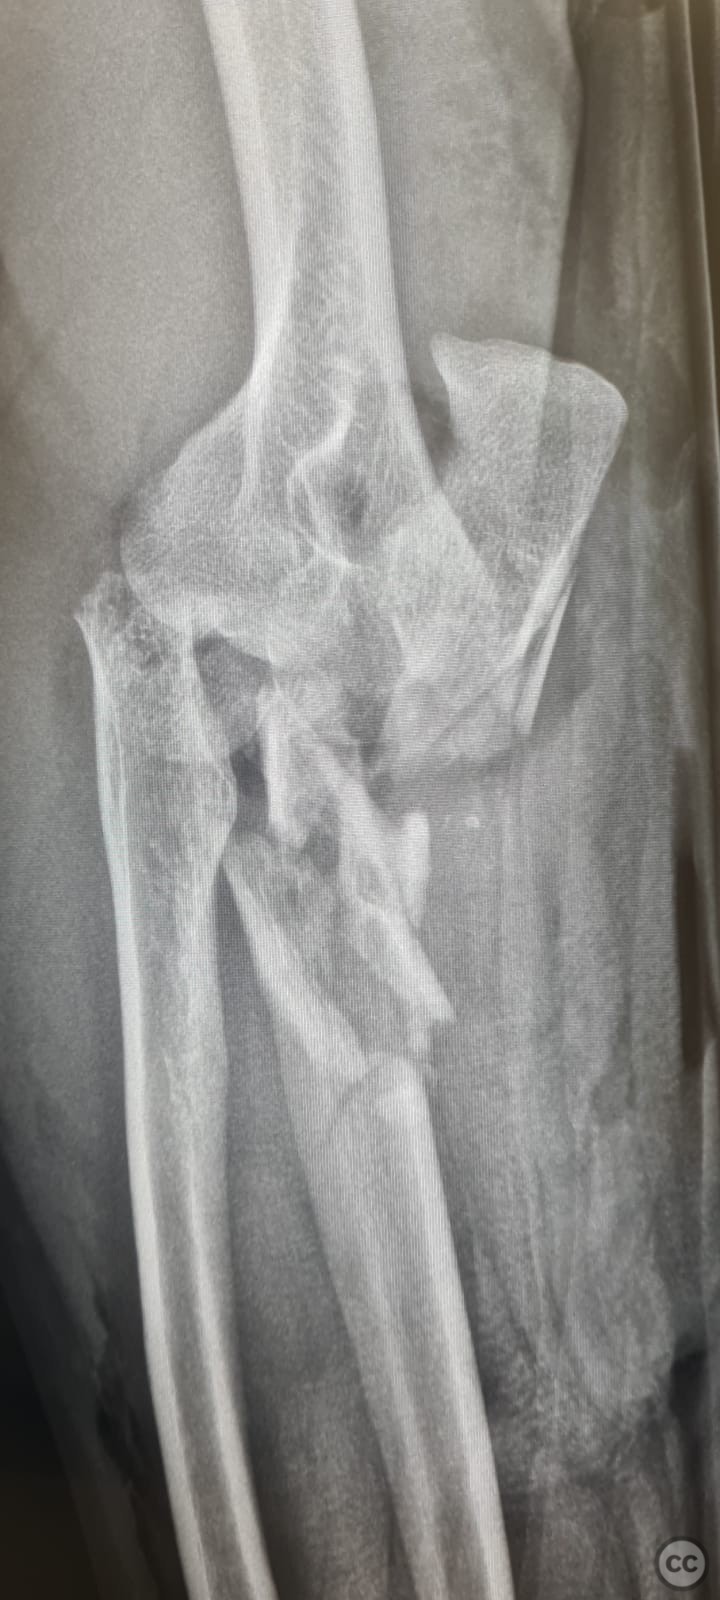

By orthopaedic_trauma

Monteggia Fracture-Dislocation with Post...

Seattle, United States

Ulna - AO/OTA 2Ux